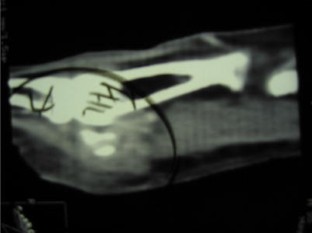

Fig. 4